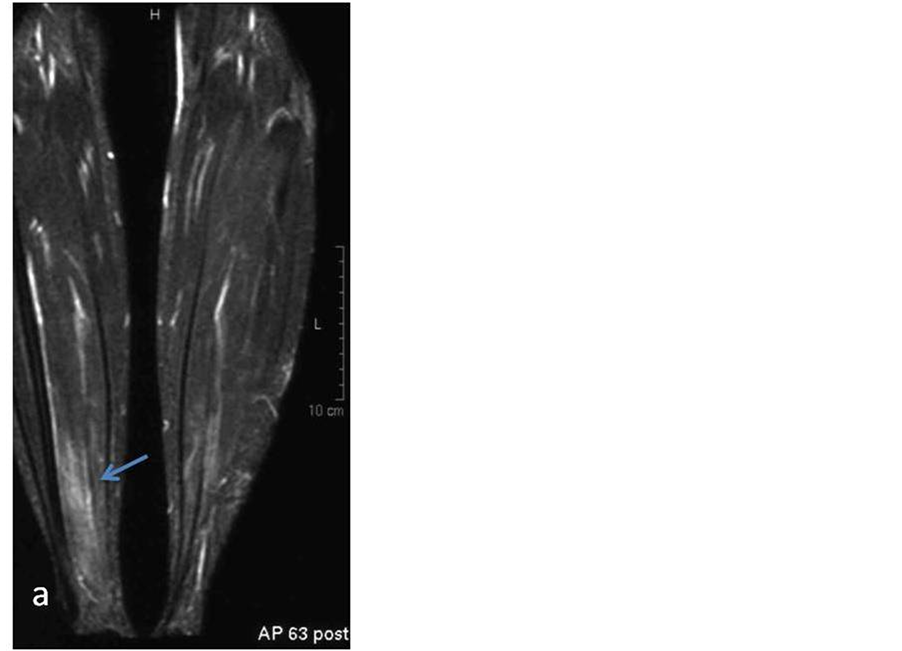

The last patient underwent both lower extremities MRI which showed myositis of the tibial muscles bilateral (Figure 3). Although this pt did not reveal any neurological symptoms, because of the presence of APS, she underwent brain MRI to detect possible cerebrovascular involvement. The brain MRI was abnormal with subcortical lesions extended to the cortex in the left parietal lobe, focal lesions in the deep white matter bilateral, as well as porencephalic lesions with peripheral gliosis on the left parietal lobe, compatible with old infarct. No pathologic enhancement was noticed (Figure 4).

Figure 4. Same patient with Figure 3. (a) Coronal FLAIR sequence shows a porencephalic lesion with peripheral gliosis on the left frontal lobe without contrast enhancement (c). (b) Axial FLAIR sequence shows hyperintensity lesions in the subcortical matter of the left hemisphere.